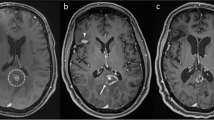

Stereotactic radiosurgery (SRS) for the treatment of a small number of well-circumscribed intracranial metastases has been tested and shown to be useful with a local control rate of 72.5 % when used as a monotherapy and 88.7 % when used in combination with whole brain radiotherapy [1]. Major advantages of SRS are the minimally invasive nature of the treatment and the patient-friendly schedule of a single fraction outpatient treatment. However, when patients are followed over time and the treated lesion demonstrates radiographic enlargement and/or the patient develops additional symptoms attributable to a lesion at the site of prior SRS, tumor progression must be distinguished from radiation necrosis. Historically, surgical resection of lesions thought to represent tumor progression demonstrated that 10 % of specimens contained radiation necrosis alone (Fig. 1) [2]. The correct diagnosis is paramount as the treatment for tumor progression versus radiation necrosis differs markedly. Treatment for tumor progression may include additional radiotherapy, chemotherapy, and/or surgical resection/ablation, whereas radiation necrosis is often a self-limited entity managed symptomatically with a short course of steroids, anti-VEGF agents, and only occasionally surgical intervention.

57 year old right-handed female with history of melanoma, diagnosed with left frontal brain and lung metastases 8 years after initial diagnosis of an arm lesion treated with resection. Treated with Gamma Knife® radiosurgery to the left frontal lobe to 2400 cGy prescribed to the 76 % isodose line, which covered 100 % of the target. The plan utilized 1 shot using 16 mm sectors. Target volume = 1.2 cc. Maximum dose = 3160.0 cGy. Maximum diameter = 1.5 cm. MD/PD = 1.317. PIV/TV = 1.917 (a). At 3 months post-Gamma Knife®, left frontal metastasis demonstrated progression of the left frontal lesion with surrounding vasogenic edema and hemorrhage (b). The patient was treated with whole brain radiotherapy to a dose of 3750 cGy in 15 fractions of 250 cGy/fraction with 6MV photons prescribed to the mid-plane. The patient did well until 7 months post-Gamma Knife®, when she experienced return of left lower extremity weakness. MRI demonstrated an enlarging mass with rim enhancement compatible with cystic tumor and recurrence metastasis (c). She again underwent excisional biopsy of the lesion, which demonstrated radiation necrosis and hemorrhage without evidence of tumor recurrence